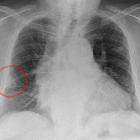

Fleischner sign

The Fleischner sign refers to a prominent central pulmonary artery that can be commonly caused either by pulmonary hypertension or by distension of the vessel by a large pulmonary embolus. It can be seen on chest radiographs, CT pulmonary angiography (CTPA), and MR pulmonary angiography (MRPA).

It is seen most commonly in the setting of massive pulmonary embolism (defined angiographically as involving 50% or more of the major pulmonary artery branches). It has a low sensitivity but high specificity.

It is one of several described signs of pulmonary embolus on chest radiographs.